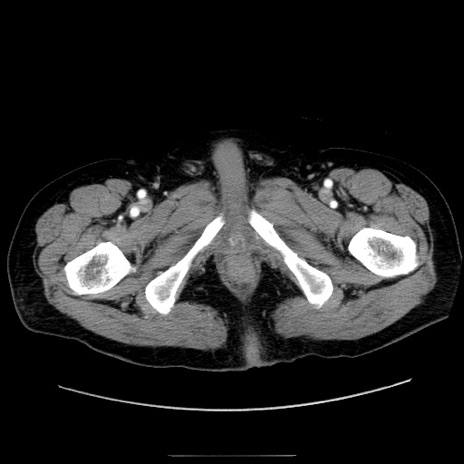

症例30(横断像)

【症例】80歳代男性

【主訴】臍周囲痛

【現病歴】約6時間前から臍下部痛が出現。次第に腹部膨隆・背部痛も生じてきたため来院。背部痛の場所は変化しない。

【既往歴】腎盂腎炎

【身体所見】意識清明、BT 36.3℃、BP  131/87mmHg、P 87bpm、SpO2 100%(RA)、臍周囲自発痛・圧痛あり、反跳痛なし、自発痛部位に一致して板状硬あり、腹部膨隆、腸雑音減弱、CVA tenderness両側陰性。

【データ】WBC 19600、CRP 0.33